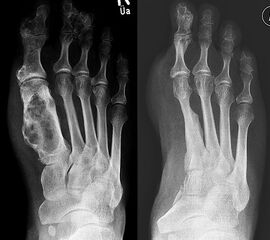

Das solitäre Enchondrom ist von Enchondromatosen, also disseminierten Enchondromen der Extremitäten und des Achsskeletts, abzugrenzen. Die Entartungswahrscheinlichkeit ist für Enchondromatosen wie dem M. Ollier (Abb. 18a und b) oder dem Maffuci-Syndrom deutlich erhöht und wird in der Literatur bis zu 25% angegeben. Klinische und radiologische Hinwiese für eine Entartung beinhalten Kortikalisveränderungen, wie -verdickung, -destruktion und die enossale Kortikalisarrosion, welche in der CT-Bildgebung mehr als 2/3 der Zirkumferenz des betroffenen (Röhren-) Knochens umfasst.

Das primäre, konventionelle Chondrosarkom des Fußes, welches nicht sekundär aus einem Enchondrom oder einer Exostose (exophytäres bzw. exostotisches Chondroarkom) sondern de novo entsteht, zeigt, ähnlich wie das Enchondrom, eine Prädilektion für die kurzen Röhren­knochen (Abb. 19). Das durchschnittliche Alter liegt hier bei 52 Jahren mit einer Bevorzugung des männlichen Geschlechts. In Abhängigkeit der Lokalisation und Graduierung des Tumors umfasst die geeignete operative Therapie die intraläsionale Curettage (G1) bis hin zur Amputation (G3) 34. Das Chondrosarkom ist nicht Strahlen- oder Chemotherapie-sensibel. Eine vollständige chirurgische Resektion bleibt deshalb die einzig sinnvolle Therapiemöglichkeit.